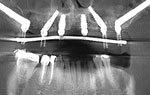

The zygoma implants are placed in the back section of the jaw approached within the mouth, along with the placement of one or more additional implants in the front region of your jaw. If the case is found too complicated or severe, two zygomatic implants may be placed on each side, which is known as Quad Zygoma.

When four zygoma implants are placed, two on each side it is called Quad zygoma. It provides high strength and excellent support for the restoration of teeth.